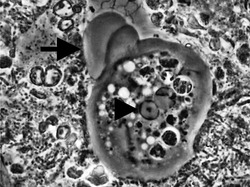

| Entamoeba gingivalis from periodontal pocket [1] | |

It is found in the mouth[5] inside the gingival pocket biofilm near the base of the teeth, and in periodontal pockets.[1] Entamoeba gingivalis is found in 95% of people with gum disease and rarely in people with healthy gums.[6][7] Cyst formation is not present; therefore transmission is direct from one person to another by kissing, or by sharing eating utensils. Only the trophozoites are formed and the size is usually 20 micrometers to 150 micrometers in diameter. Entamoeba gingivalis have pseudopodia that allow them to move quickly and phagocytise the nucleus of polynuclear neutrophils by exonucleophagy in periodontal disease.[8] Their spheroid nucleus is 2 micrometers to 4 micrometers in diameter and contains a small central endosome. There are numerous food vacuoles, which consists mostly of phagocytised PMN nucleus, blood cells, and bacteria. It also causes pyorrhoea.